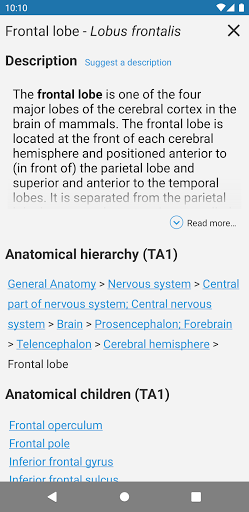

* Tablas introducidas en las definiciones de estructuras anatómicas para una mejor estructuración de datos

*Visibilidad mejorada de las definiciones de partes anatómicas

. *Navegación entre partes anatómicas usando enlaces de descripción.

la vista de detalles de una estructura anatómica ahora se muestran los términos relacionados